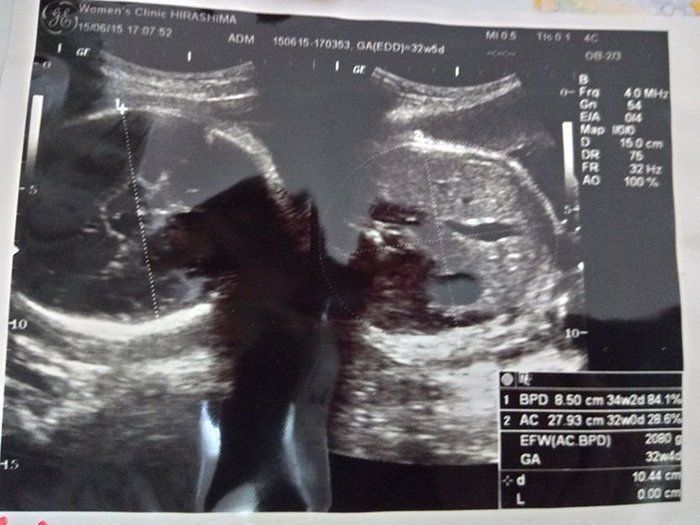

クリコさんの妊娠32週目のエコー写真

2000gを超えました。安心と同時に、体の重い状態がまだあと2カ月も続き、まだ大きくなるのかと思うと少し憂鬱に。体重も7kg以上増え助産師さんに注意されたものの、何か口に入れていないと気持ち悪くなるような状態で、つい食べ過ぎて自己嫌悪になることもありました。